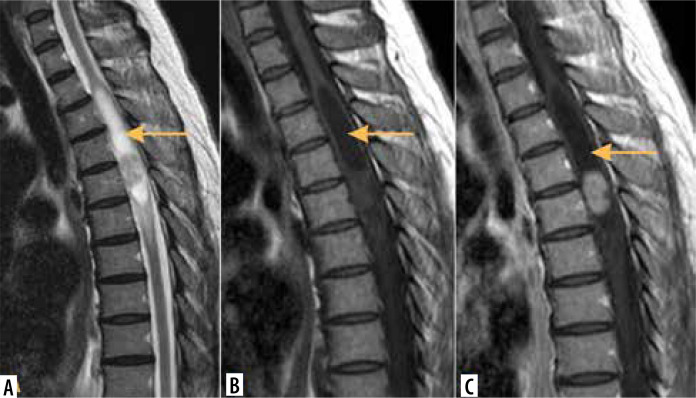

髓内肿瘤(IMTs)是椎管最不常见的肿瘤。其中大多数是室管膜瘤和星形细胞瘤,第三常见的是血管母细胞瘤,而脊髓的其他肿瘤相对罕见。本文综述了脊髓肿瘤影像学的最新进展。磁共振成像(MRI)是诊断imt的首选成像方法,其他方式起辅助作用。作者讨论了IMTs的MRI方案,包括先进的技术,并介绍了特定肿瘤的成像特征。本文还介绍了IMTs与其他脊髓疾病的区别。

Intramedullary tumours (IMTs) are the least common neoplasms of the spinal canal. The majority of them are ependymomas and astrocytomas, the third commonest is haemangioblastoma, while other tumours of the spinal cord are relatively rare. This review presents on update on the imaging of spinal cord tumours. Magnetic resonance imaging (MRI) is the imaging method of choice in diagnosing IMTs, with other modalities playing a supplementary role. The authors discuss the MRI protocol in IMTs including advanced techniques and present the imaging features of particular tumours. The differentiation of IMTs from other spinal cord diseases is also presented.